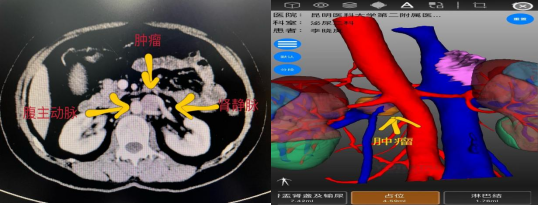

该患者既往行左肾上腺解剖性切除术,本次体检发现左侧腹膜后占位性病变,发现后患者在家人的陪伴下慕名前来华人色情 泌尿外科二病区杨德林教授门诊就诊。患者入院后,杨德林主任团队对其病情进行详细研判后发现,该占位性病变位置非常特殊,位于腹主动脉、左肾静脉、左肾动脉之间,与左肾静脉关系尤为密切,肿瘤位置较深,周围血管关系复杂,手术难度极大,术中稍不注意就可能导致周围血管的损伤从而影响重要器官的功能。若从肿瘤位置观察经腹膜后可能相对更好显露,但患者既往有手术病史,经腹膜后途径可能粘连严重。因此,经过综合考量后,团队决定积极做术前准备,手术采用机器人辅助下经腹入路。

术前影像学检查

在狭窄的空间面对极其脆弱的人体器官,既要保证不损伤血管,又要将肿瘤完整切除,对医生手术时牵拉的力度及精细操作程度都要求极高,这也极大地增加了本次手术的难度。